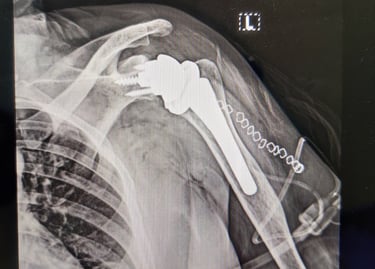

Shoulder replacement surgeries-

Anatomical and Reverse Shoulder replacement

Revision shoulder replacements

Stemless shoulder replacement

Partial Shoulder replacement